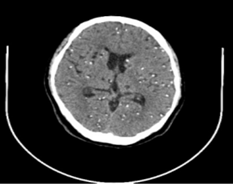

Figura 2-3. TC simple de cráneo: cortes axiales, coronales y sagitales.

Hallazgos Fig 2: presencia de múltiples imágenes quísticas, con signos de retracción con presencia de imagen hiperdensa puntiforme con una distribución supra e infratentorial, acompañado de edema periférico, calcificación fisiológica de plexos coroideos de los ventrículos laterales y glándula pineal.  Informe María José Arcos Jima

§  Estadio nodular-granulomatoso de neurocisticercosis, se asocia a signos de edema periférico adyacente de predominio supratentorial

§  Neurocisticercosis a forma nodulillar calcificada

§  Neurocisticercosis nodular coloide activa parietal bilateral

Se realizó interconsulta en las áreas de oftalmología, infectología y neurología quienes establecen su diagnóstico, exámenes complementarios y tratamiento respectivo: se solicitó una TAC simple de encéfalo (Figuras 3-4), evidenciándose múltiples calcificaciones intracraneales, sugestivas de neurocisticercosis en varias etapas, e hipodensidad mal definida en región parietal izquierda, considerada edema cerebral que sugieren un proceso de autoinfección en la paciente, sumado a un cuadro de atrofia del nervio óptico con consecuente pérdida irreversible de la visión asociada a la neurocisticercosis. Determinando el diagnóstico de cisticercosis del sistema nervioso central.

Se estableció el diagnóstico de neurocisticercosis mediante tomografía computarizada simple de encéfalo en cuyos hallazgos se evidenció imágenes nodulares cálcicas, que miden entre 2 mm y 5 mm, localizadas en todo el parénquima, y en la región parietal se aprecian formas nodulares coloides en número de 2 a cada lado de la línea media.